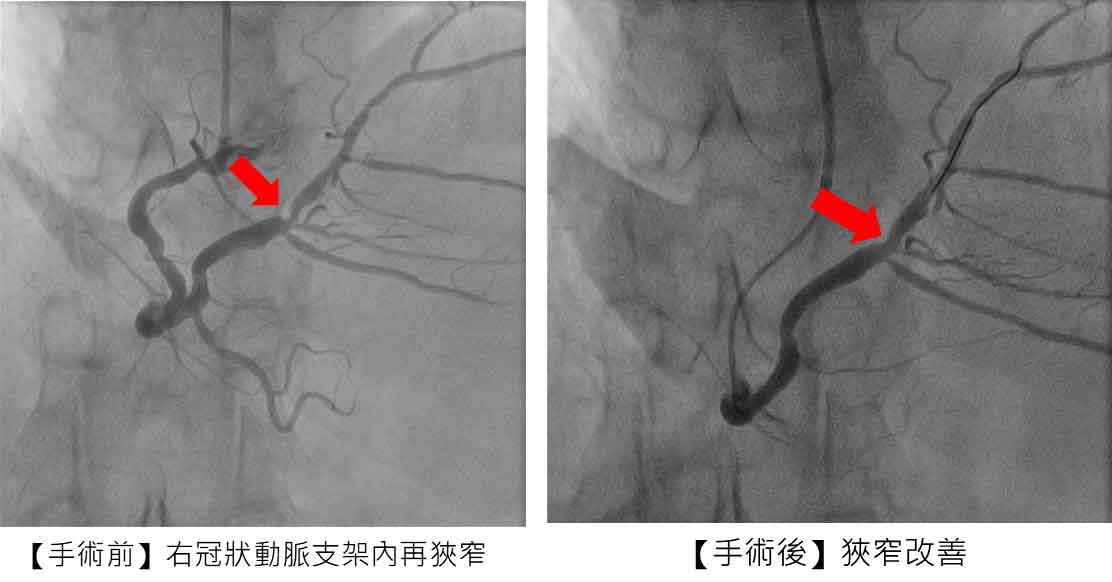

治療前與治療後,施行「刀片氣球」及「塗藥氣球」治療後,右冠狀動脈支架狹窄改善。

針對張先生的治療過程,市醫副院長兼心臟科專家陳建鈞醫師進一步說明,病人有多次支架再阻塞的病史,加上長途奔波與生活壓力,病情更加複雜。經團隊縝密評估後,決定採用「刀片氣球」及「塗藥氣球」治療,既能打通血管阻塞,也可降低再度狹窄的風險,大幅縮短康復時間。手術全程順利,患者隔日即可出院,術後更能安心規劃生活與健康管理。